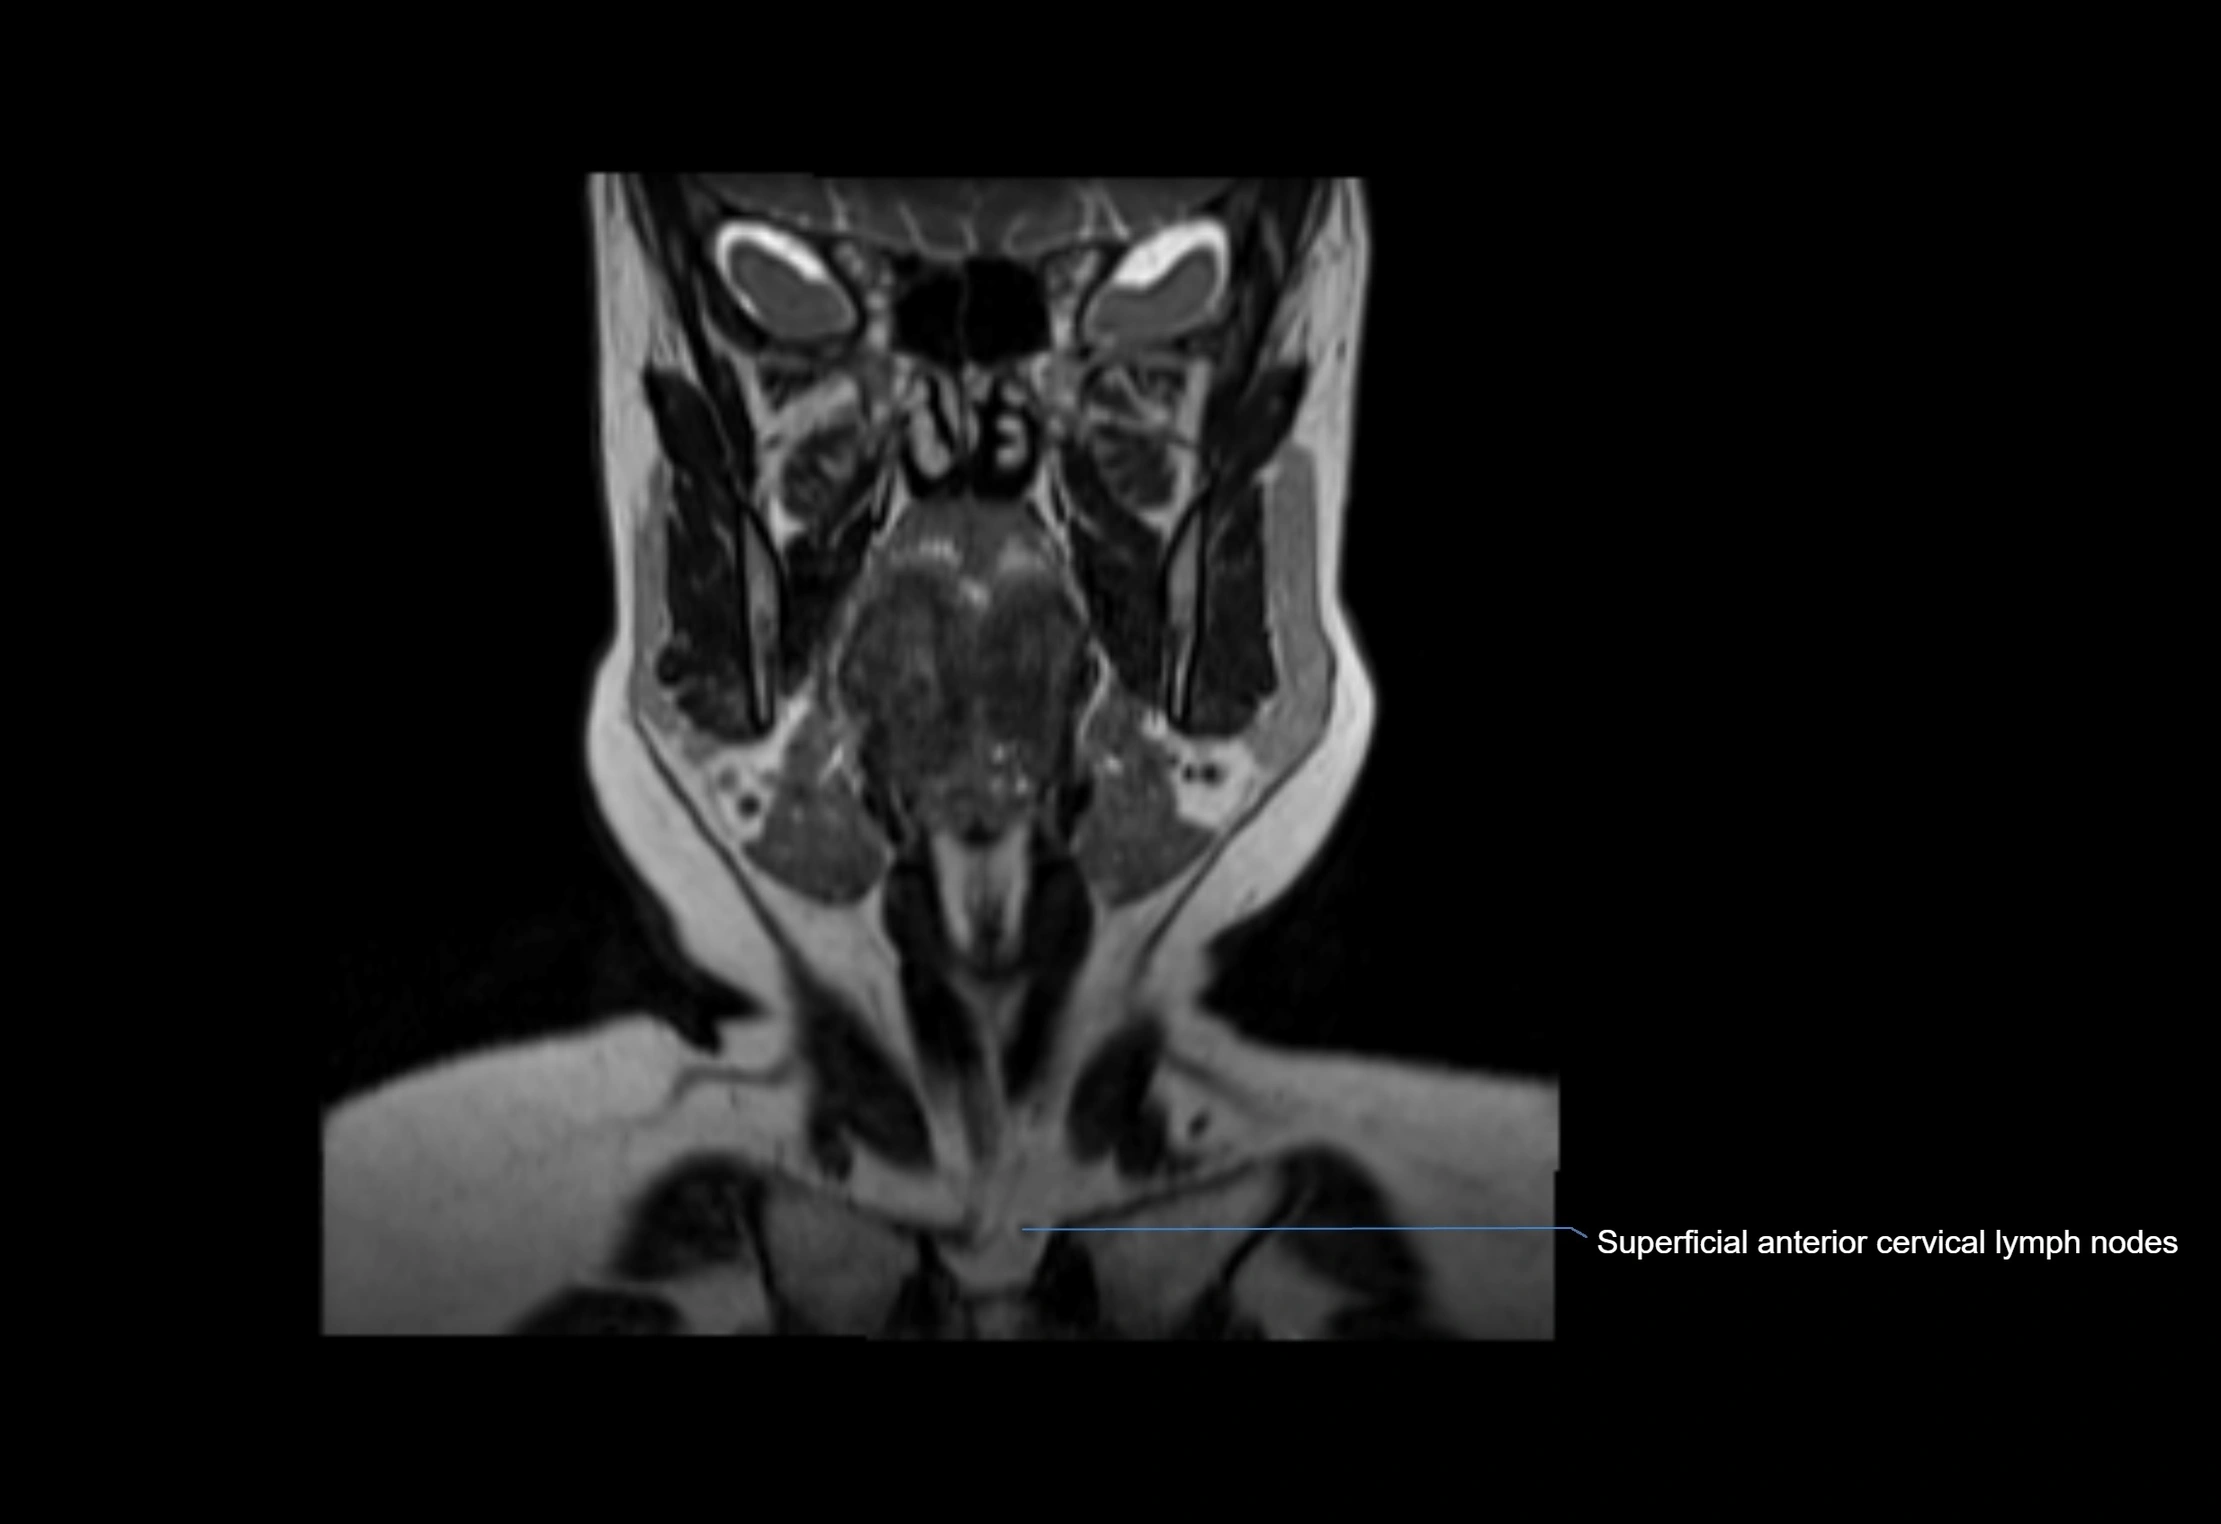

MRI Appearance

T1-weighted images:

• Normal accessory nodes appear as small, oval hypointense to intermediate signal structures within subcutaneous fat

• Surrounded by hyperintense fat, enhancing contrast for visualization

• Pathological nodes may appear enlarged or rounded, sometimes with cortical thickening

T2-weighted images:

• Nodes show intermediate signal, with surrounding fat bright

• Useful for detecting edema, inflammation, or infiltration

• Fatty hilum may appear slightly hyperintense relative to cortex

MRI images

image